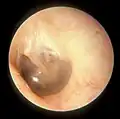

Right eardrum as seen through a speculum

When the eardrum is illuminated during a medical examination, a cone of light radiates from the tip of the malleus to the periphery in the anteroinferior quadrant, this is what is known clinically as 5 o'clock.